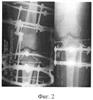

Фиг.1 – рентгенограмма коленного сустава больного Р. до лечения;

При осмотре были жалобы на боли в области коленного сустава, неопорность и деформацию левой нижней конечности. Левая нижняя конечность фиксирована задней гипсовой лонгетой в положении сгибания его 160°. На контрольной ренгенограмме – перелом межмыщелкового возвышения с его смещением в медиально-дорзальном направлении (фиг.1).